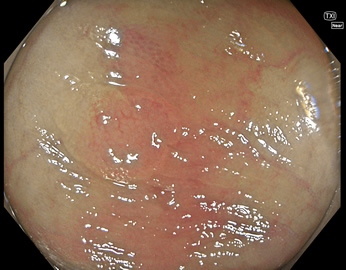

TXIは、「画像の構造を強調する」技術です。これは特別に目新しいものではありません。パソコンの画像編集ソフトや、スマホのアプリでも御馴染みの技術です。しかし、「どのような構造強調が実際に、内視鏡に一番、合うか?(強すぎると不自然になる!)」は、難しい(アナログ的な)課題です。オリンパス社は数タイプのTXIモードを用意しました。半年間の試行錯誤の末、今では下記のモードがベストと判断しました。そして今では「TXI無しの内視鏡は不要(フルタイムTXI)」というまで常用しています。

写真だけ、見ると「言われてみるとTXIの方が認識しやすい。でも僅かの差」と感じるでしょうが、この「僅かの差」が、人間の脳での検出には大きな差になります。青い色素(インジゴ・カルミン)が非常に強調され、粘膜の凸凹が明瞭になるのが特徴です。

通常観察 TXIモード